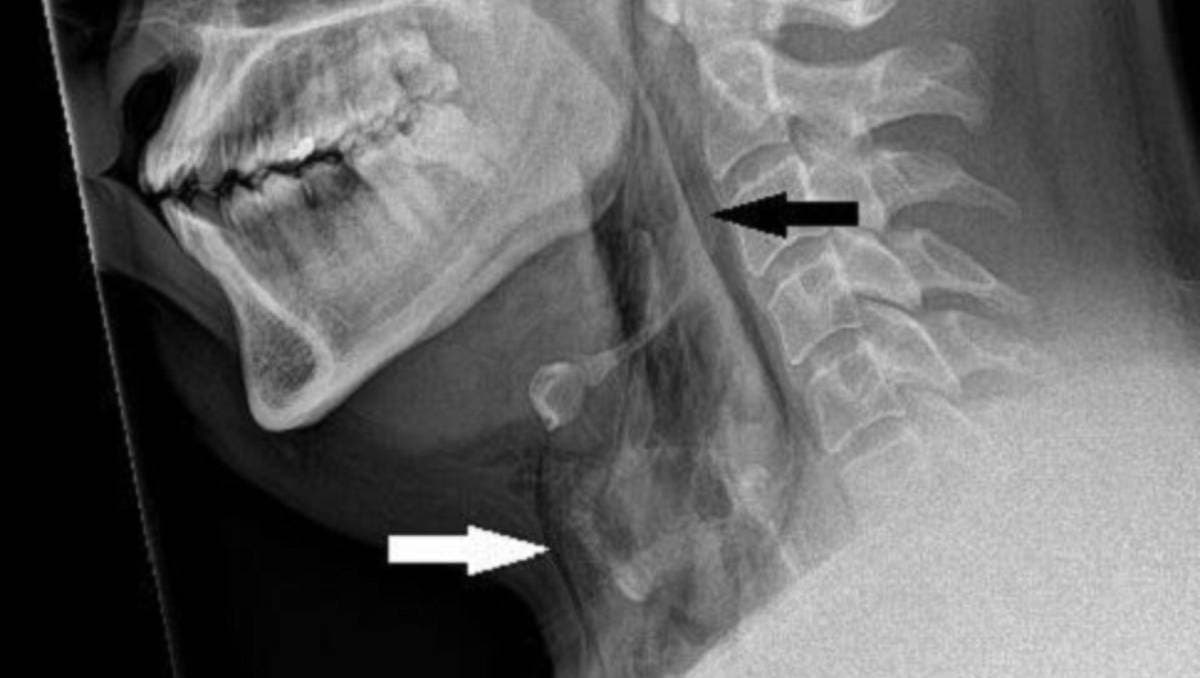

El sujeto sufrió la ruptura de una arteria dentro de su cavidad nasal, lo que provocó un sangrado profuso que no pudo ser detenido sin intervención quirúrgica.

Expertos en otorrinolaringología advierten sobre los peligros de hurgarse la nariz de forma constante. La mucosa nasal, que es rica en capilares, puede sufrir daños por esta práctica, lo que puede desencadenar irritaciones, lesiones, úlceras y, en el peor de los casos, hemorragias.

Además, el riesgo de una infección intracraneal aumenta considerablemente con la manipulación excesiva de las fosas nasales.